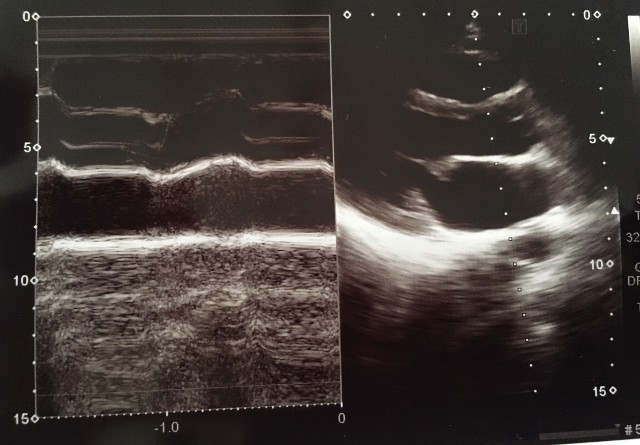

③

Bモードが綺麗に描出されている。

Mモードのラインがやや斜めなので、プローブを少し胸骨に近づけてみる。

④

大動脈前壁と後壁が平行になっていない。

大動脈と左室に角度があるため、もう一肋間上から描出してみる

⑤

Bモードで左房が描出できてないので、Mモードの計測で左房径が小さくなる。

⑥

AOとLAにMモードのラインが垂直に入っていない。